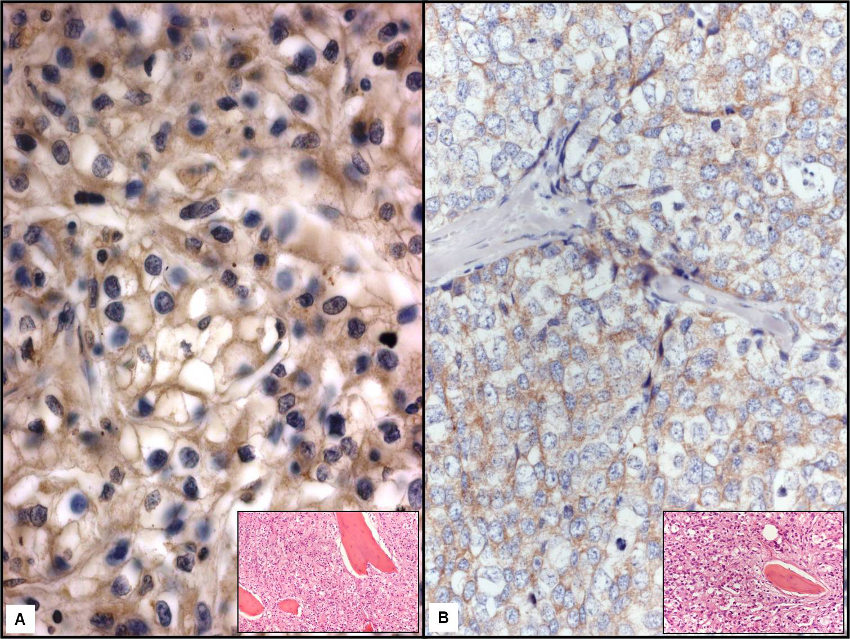

Figure 2: LF immunopositivity was well represented at the periphery of clear cell in a metastasis to bone by renal carcinoma (a, x400); the inset illustrated the routinely stained section with partially destroyed bone lamellae (x 40). A light to moderate LF immunostaining was found in breast ductal invasive carcinoma (b, x400); the inset illustrated the routinely stained section with partially destroyed bone lamellae (x 40). (Mayer's hemalum counterstain).